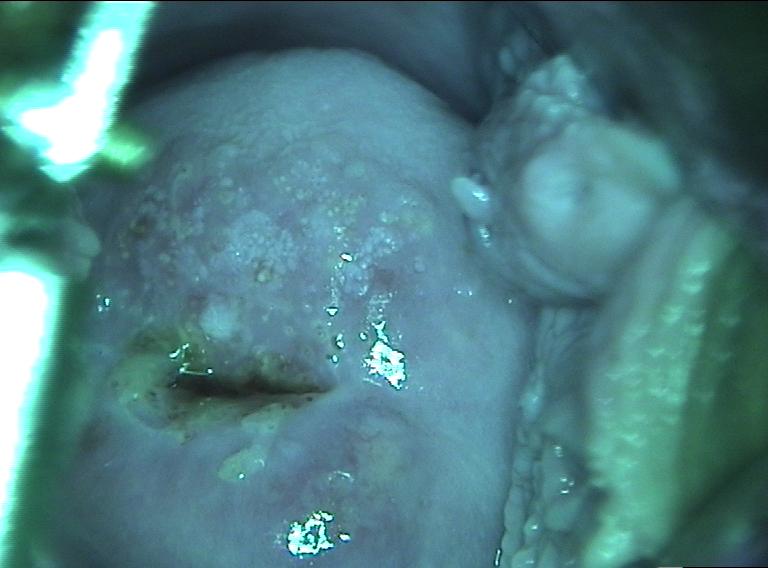

After the cervix is studied with the colposcope, the cervix is washed with a chemical called 3 – 5% acetic acid. The acetic acid dissolves mucus and stains the abnormal areas white. (acetowhite lesions). Staining with a dilute iodine solution (known as Lugol's solution or Schiller's solution) is also performed to further examine for abnormalities. Normal cells will generally take up the iodine stain (and turn brown) in a uniform manner, whereas severe precancerous and cancerous areas will not.

Color filters help the physician examine tiny blood vessels (capillaries) in the area of the squamocolumnar junction. Blue or green filtered light can cause abnormal capillaries to become more obvious, usually inside an acetowhite area. Normal capillaries are slender and spaced out evenly. In contrast, abnormal capillaries can appear as red spots (thickened capillaries seen on end) or can produce a pattern resembling hexagonal floor tiles.

Colposcopy allows tissue sampling (biopsy) that is targeted to the abnormal areas. In fact, the biopsy of abnormal areas is a critical part of colposcopy because treatment will depend on how severe the abnormality is on the biopsy sample.